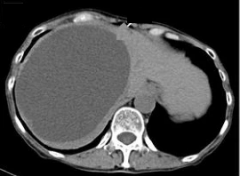

Simple Hepatic Cyst 单纯性肝囊肿 单纯性肝囊肿是相对于复杂性肝囊肿而言(complex hepatic cyst) 单纯性肝囊肿通常是壁薄的囊性中午,其内部充满液体且有上皮细胞衬里。它们由胚胎发育期间出现的异常胆管细胞形成。如今,超声检查(US)、CT 和 MRI 等诊...

在诊断手段广泛出现之前,肝囊肿是在手术中诊断出来的。 在1974 年,Sanfelippo 等人报告称,肝囊性病变的发病率为每 10000 例探查中有 17 例【 Sanfelippo PM 1974 】。 随着包括超声(US)和计算机断层扫描(CT)在内的诊断手段使用增多,肝囊肿在医学检查...